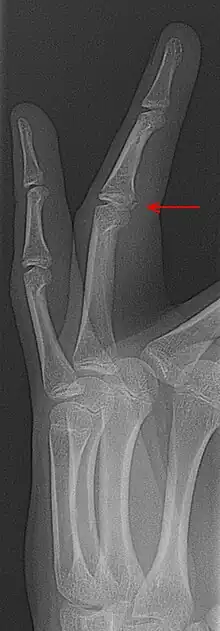

Fracture-avulsion

La « fracture-avulsion »[1] est une fracture avec déplacement de fragment osseux ou cartilagineux [2], l'os pouvant être arraché par une tension trop importante d'un ligament, par exemple au niveau du coude ou du genou (patella...)[3].